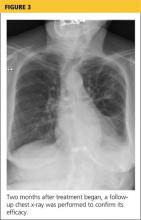

Her hypoxia prompted further radiographic studies. The resulting chest CT scan showed ground glass opacities located primarily in the upper lung areas, greater on the right than on the left side (see Figure 2). The radiologist suggested that the hypoxia was caused by an infection, but because the patient’s presenting symptoms were chronic in nature, drug-induced causes were considered as well. Amiodarone was discontinued.